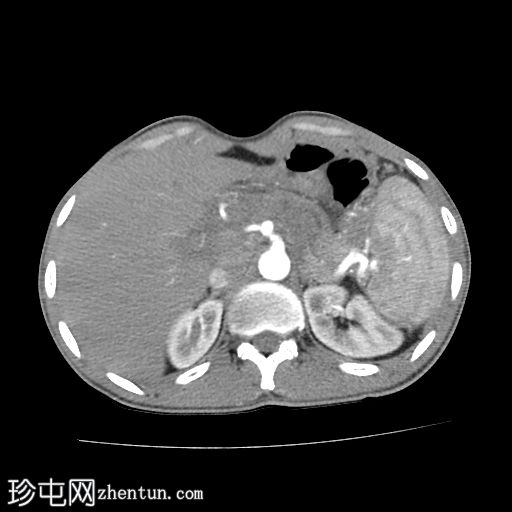

轴位增强扫描

动脉期

胰腺肿大。胰头、胰颈和胰体未见强化,边界不清且不规则。主胰管扩张,管内可见钙化。

胰腺实质内弥漫散在分布着大量钙化灶。

胰尾可见部分强化区域。

胰尾部钙化性假性囊肿。

影像学表现提示慢性钙化性胰腺炎伴胰尾部钙化性假性囊肿。